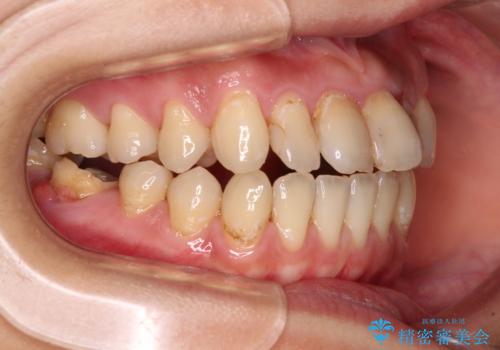

- 上下前歯の開咬とデコボコを気にして来院された患者様です。

開咬(オープンバイト)はインビザラインによる矯正治療がワイヤー装置と比べて圧倒的に有利であるため、インビザラインによる矯正治療を行うこととしました。

通院されなかった時期があって治療期間が長くなったり、奥歯に抜歯が必要な歯があったりと、治療は一筋縄にはいきませんでしたが、何とか治療を終えることができました。

今後はインプラント治療やむし歯治療を進めて行く予定です。